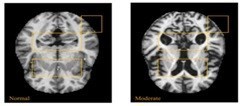

In AD affected brain the ventricles in center of the region enlarges and the cortical gray area in the corners of the brain reduces [9].

Non-demented very mild mild moderate